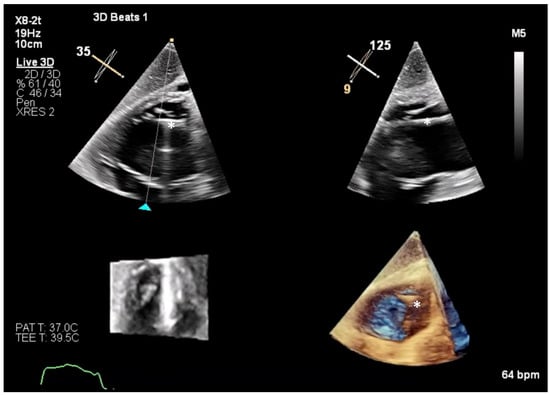

6.1. TEE-Guided Tricuspid TEER